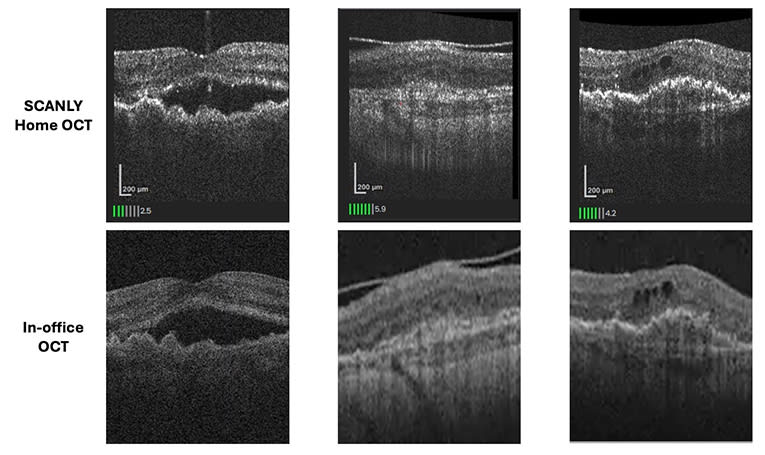

Figure 1. Side-by-side comparison of images taken with the Scanly home optical coherence tomography (OCT) device and an in-office OCT device demonstrate high concordance in detecting hyporeflective spaces, corresponding to fluid, in patients with neovascular age-related macular degeneration.

The study, published in Ophthalmology Science, enrolled 180 patients across 7 US retina practices and assessed the device’s diagnostic accuracy and patient usability over a 5-week period. Participants received the Scanly device by courier and were instructed to self-image daily without prior training. Comparative in-office OCT scans were used to evaluate agreement in detecting hyporeflective spaces, a marker of fluid (Figure 1). Scanly achieved a positive percent agreement of 86.6% and a negative percent agreement of 86.1%, meeting the study’s prespecified endpoint.